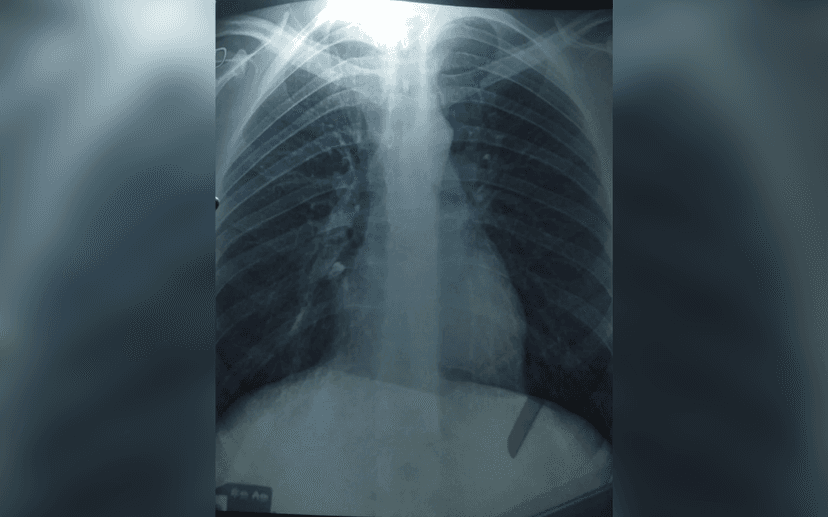

However, the man soon developed severe hiccups that occurred only when he stood up, followed by fever symptoms. A subsequent chest X-ray confirmed the tooth had been aspirated into his lung. This rare complication occurred because the sedation prevented him from coughing out or swallowing the tooth instinctively.